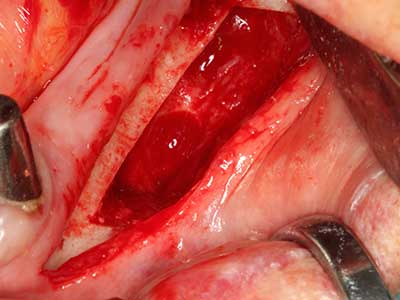

Фиг. 18: Препарация на кортикално покритие с пиезо накрайник за кост (Piezomed, W&H).